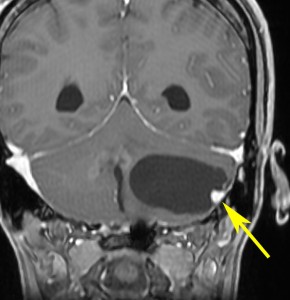

左小脳にできた小さな のう胞性血管芽腫です。矢印の先にある小さな塊だけが腫瘍で周囲は腫瘍から染み出した液体が溜まっています(のう胞といいます)。右側は血管撮影とMRIを組み合わせた画像で,腫瘍に動脈が流入しているのが見えます。

左右の写真は異なった患者さんのものです。両者ともに,大きな嚢胞(水たまり)を伴う小脳内部の小さな血管芽腫です。右の方に小さく白い塊(黄色の矢印)が見えるのですが,それだけが腫瘍で,濃い灰色に見える部分はのう胞といって液体がたまっているだけです。

これはとても(といっては何ですが比較的に)簡単な手術例です。小脳失調によるふらつきや水頭症よる頭痛と嘔吐などを出しますが,手術後に症状は改善します。

一般に小脳半球という場所にできたものは大きくても手術の成功率はとても高いです。小さいものでは場所と症状によってはガンマナイフなどの放射線治療も有効なことがあります。しかし,手術で摘出できるものは摘出した方が確実に治ります。